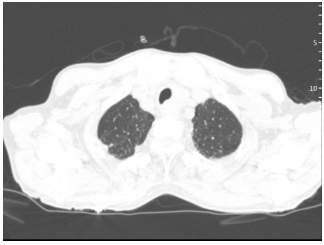

患者男性,42岁,因“痰中带血、气短3月余”入院。胸部CT提示双肺多发渗出影7),支气管镜病理检查确诊肺泡蛋白沉积症,血气分析结果:pH 7.38,PaO2 53 mmHg,PaCO2 40 mmHg,BE -1.3 mmol/L。

图片

7  患者治疗前胸部CT